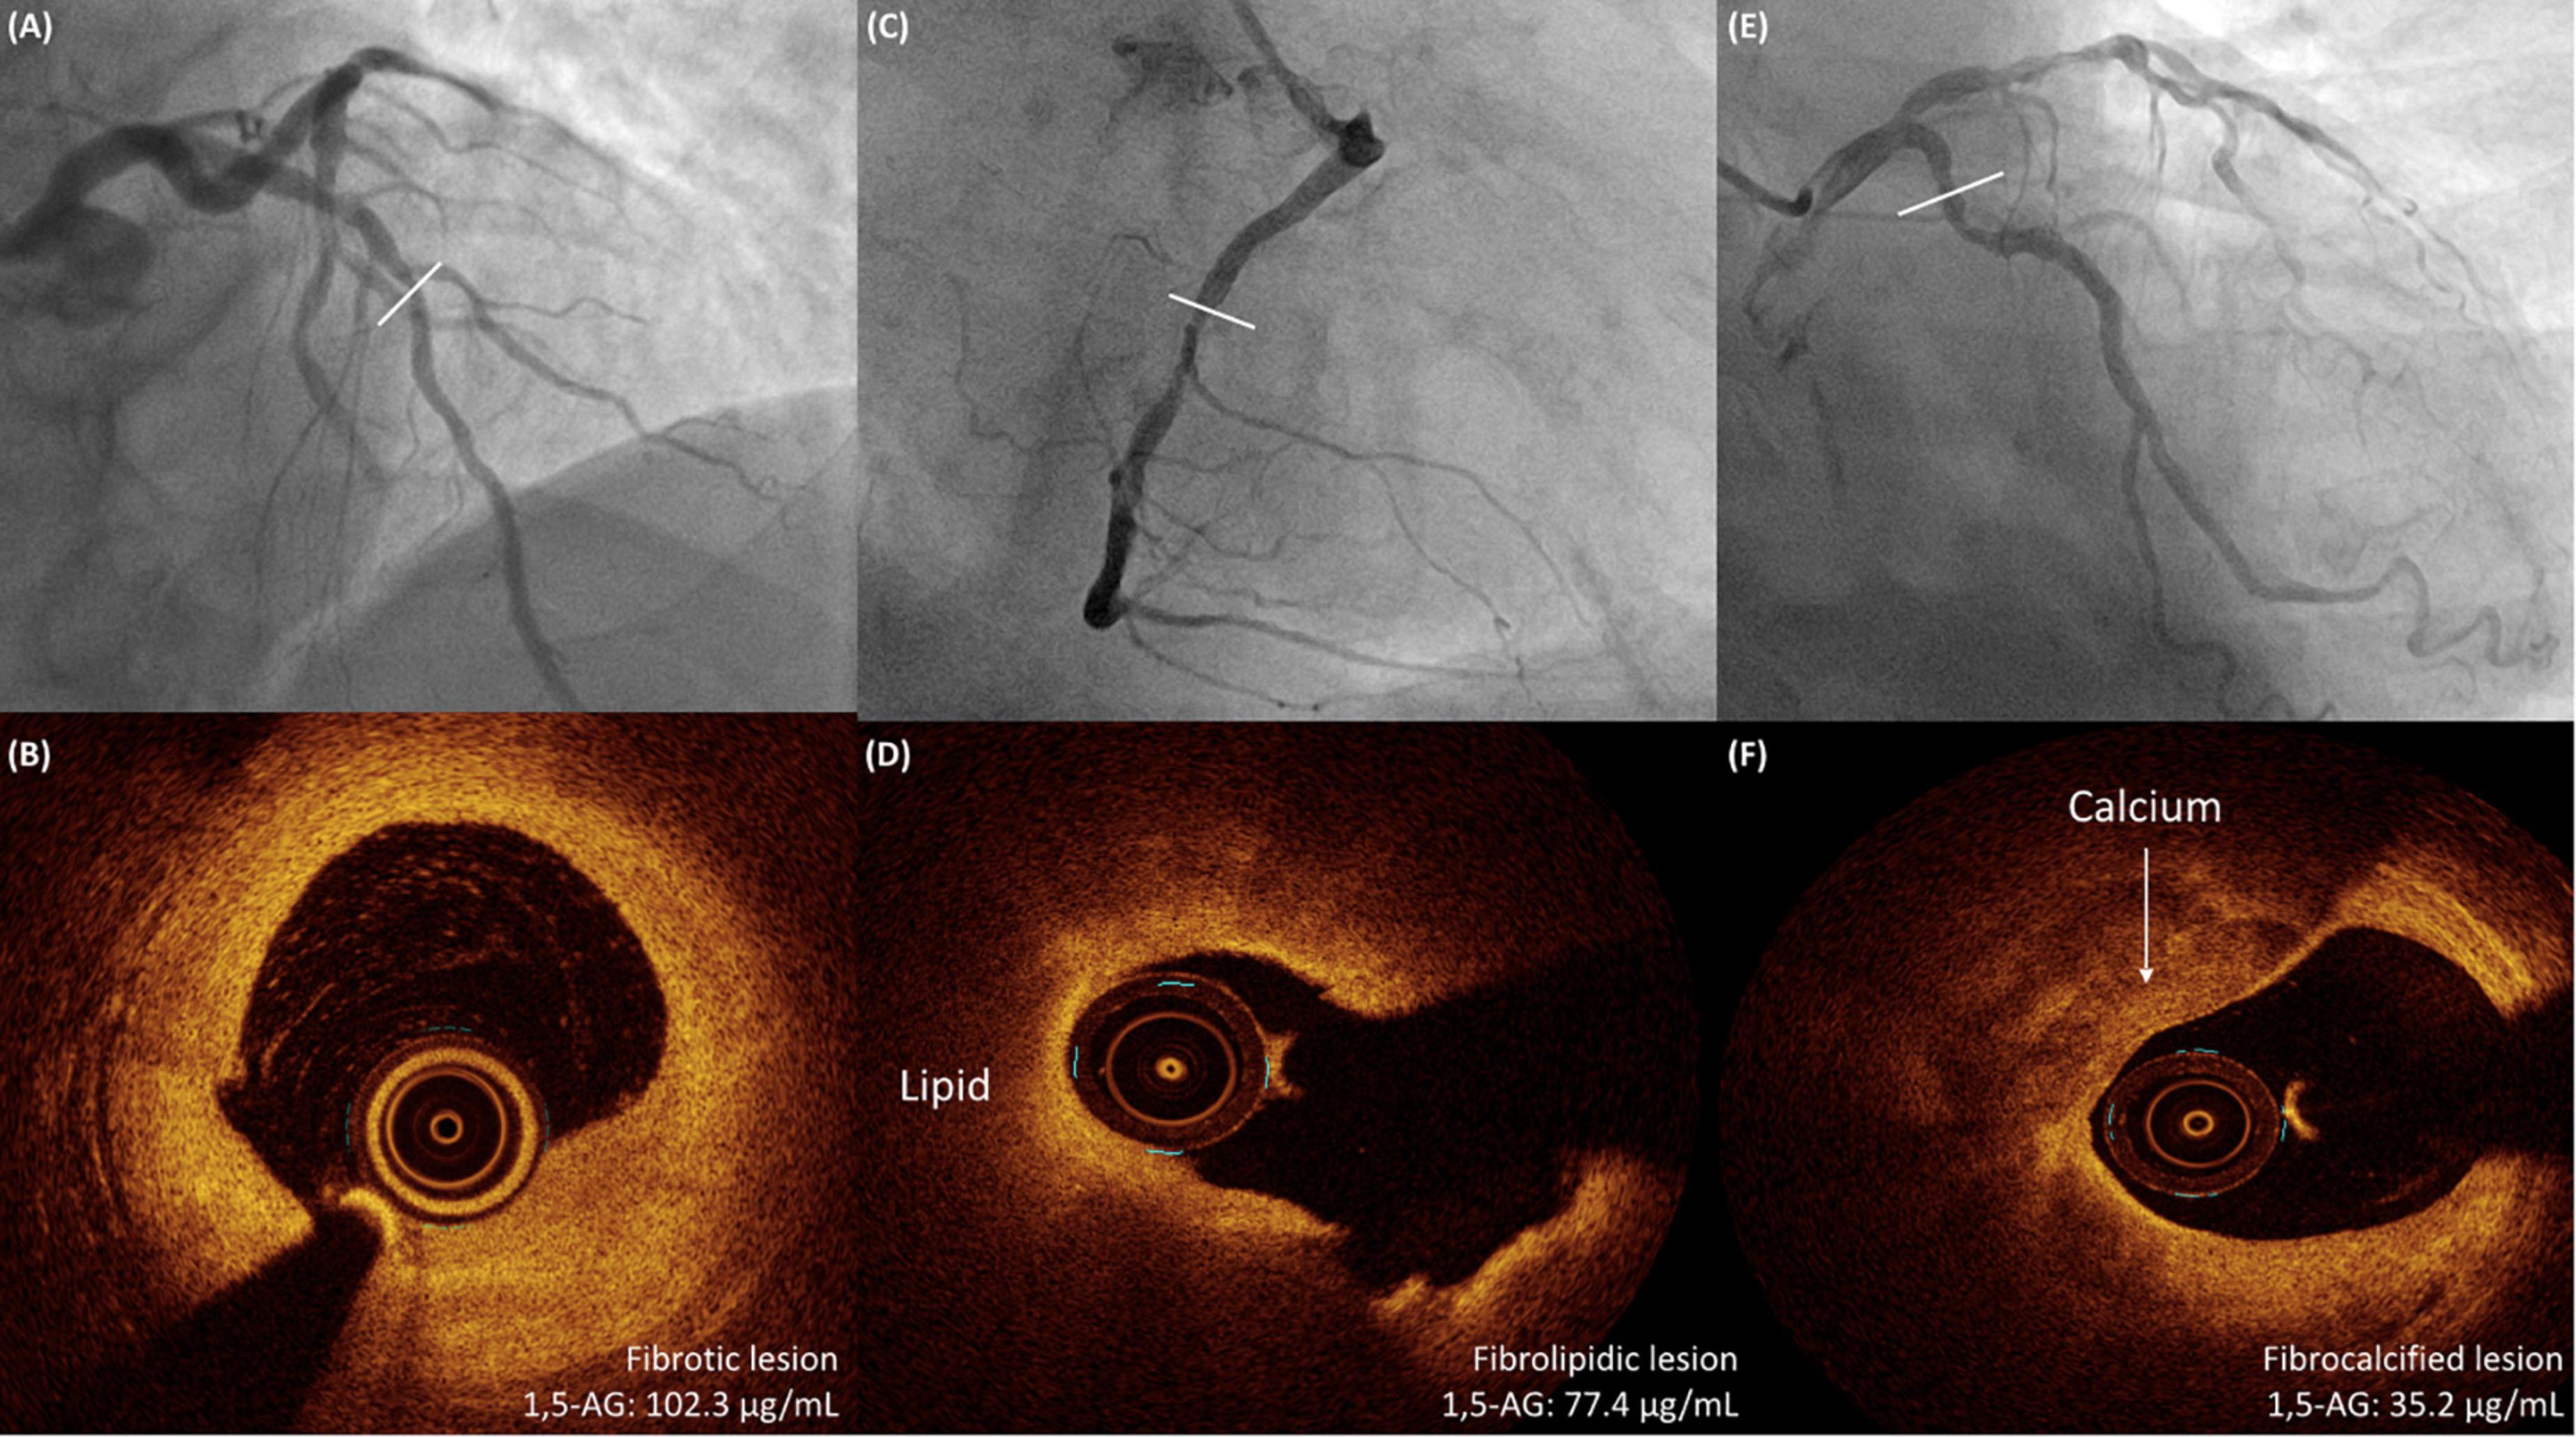

Levels of serum 1,5-AG were significantly lower in fibrocalcified lesions than in fibrotic or fibrolipidic lesions (fibrocalcified vs. fibrotic or fibrolipidic: 42.8 ± 19.1 vs. 72.9 ± 25.2 or 66.4 ± 27.5 μg/mL, p < 0.001, respectively, Figure 2B). Furthermore, we found a strong inverse correlation between serum 1,5-AG level and the RCI (r = −0.729, p < 0.001, Figure 3). In contrast, serum 1,5-AG levels correlated significantly to the RLCI in ACS patients (r = −0.358, p < 0.001), but not in non-ACS patients (r = −0.062, p = 0.322). Three representative cases with different correlations between plaque type and serum 1,5-AG levels are shown in Figure 4.

Figure 4. Three representative cases with different correlations between OCT-detected plaque type and serum 1,5-AG levels. (A,B) A 68-year-old man with hypertension and stable angina is shown to have a lesion in the middle LAD on angiography. OCT examination shows a fibrotic lesion. The serum 1,5-AG level is 102.3 μg/mL. (C,D) A 72-year-old man with DM and NSTEMI is shown to have a severe lesion in the middle RCA on angiography. OCT examination shows a fibrolipidic lesion. The serum 1,5-AG level is 77.4 μg/mL. (E,F) A 68-year-old man with DM and stable angina is shown to have a diffuse lesion in the proximal LCX on angiography. OCT examination shows a fibrocalcified lesion. The serum 1,5-AG level is 35.2 μg/mL. 1,5-AG, 1,5-anhydro-D-glucitol; DM, diabetes mellitus; LAD, left anterior descending artery; LCX, left circumflex artery; NSTEMI, non ST-segment elevation myocardial infarction; OCT, optical coherence tomography; RCA, right coronary artery.